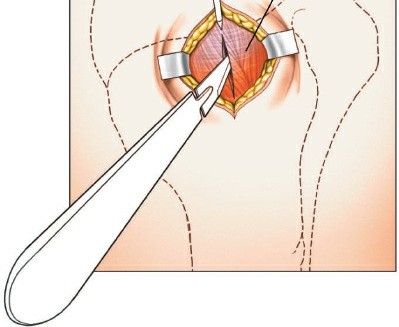

Make a longitudinal or slightly diagonal incision starting from the anterolateral corner of the acromion and extending distally for approximately 3 to 5 cm.

Preoperative skin marking outlining the anterolateral acromial approach.

Proceed with sharp dissection through the subcutaneous tissue to identify the deltoid fascia. Split the deltoid muscle in line with its fibers, specifically targeting the raphe between the anterior and middle thirds of the deltoid.

Surgical Warning: To protect the axillary nerve, strictly avoid splitting the deltoid more than 5 cm distal to the lateral edge of the acromion. If distal extension is required, a stay suture should be placed at the inferior apex of the split to prevent inadvertent propagation of the dissection into the nerve.